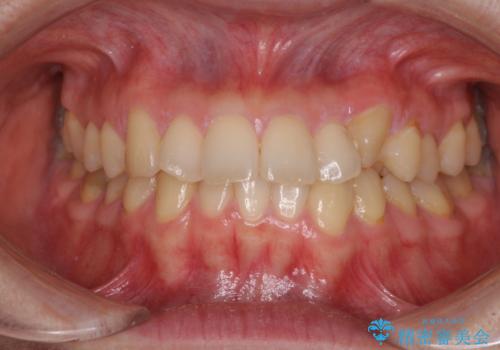

前歯のデコボコを治したい 高校生のインビザライン治療

担当医 藤巻太一朗